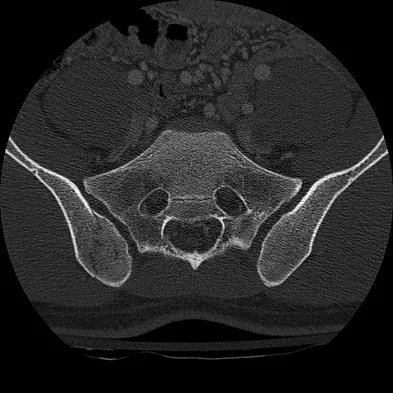

A 22-year-old cheerleader who fell from the top of a pyramid now reports anterior and posterior pelvic pain. A radiograph and CT scans are shown in Figures 43a through 43c. What is the best treatment for this injury?

Explanation